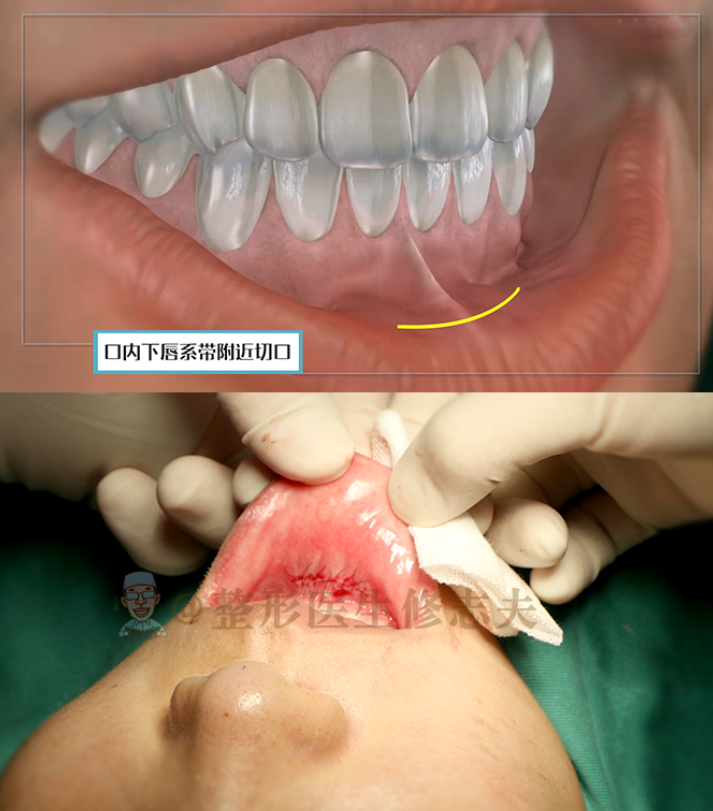

假體隆下巴的切口主要有兩個(gè),一個(gè)是在下巴下方的外切口,一個(gè)是在口內(nèi)下唇系帶附近的內(nèi)切口。

▼假體隆下巴的兩種切口

假體隆下巴一般會(huì)選擇口內(nèi)切口,這樣外觀看不來;術(shù)后腫脹反應(yīng)也輕,加上醫(yī)生會(huì)用膠布包扎定型,也會(huì)加速消腫,所以腫脹并不。